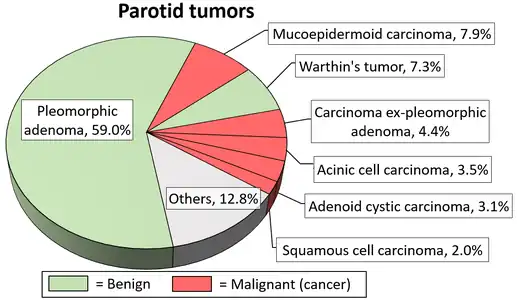

Diagrams by Mikael Häggström, MD